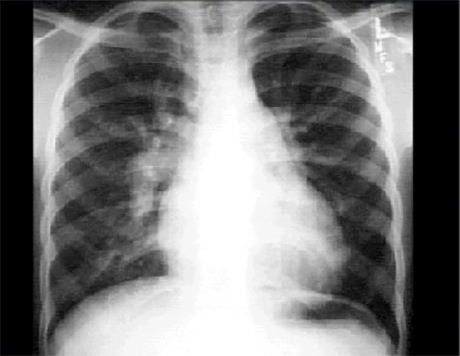

This chest X ray shows increased pulmonary vascularity and a dilated pulmonary trunk.

In this PA view, the pulmonary vasculature markings are clearly visible in the outer third of the lung fields. The convex shadow just beneath the small aortic knob reflects an enlarged main pulmonary artery. Cardiomegaly is also present, as evidenced by the cardiothoracic ratio greater than fifty percent.

These findings are compatible with an intracardiac left-to-right shunt.